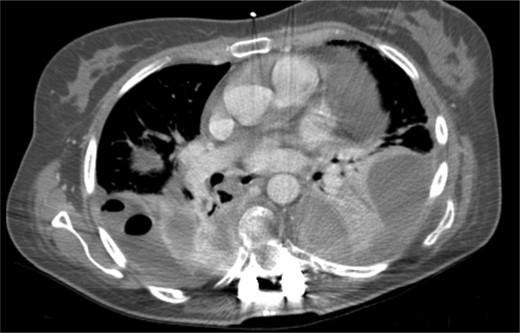

The radiographic study identified an expansive lesion in the eighth thoracic vertebra (T8), with local kyphosis and imminent instability. She performed a computed tomography (CT) scan and magnetic resonance imaging (MRI), which better defined the bone involvement and already revealed invasion of the medullary canal (Fig. 1). A percutaneous CT-guided core-needle biopsy was then undertaken, and the histologic report confirmed the diagnosis of giant-cell tumor.

Preoperative imagiologic study; involvement of T8 by the giant-cell tumor as presented in plain radiograph (A), CT scan (B) and MRI (C and D). Notice the tumor mass protruding into the vertebral canal.